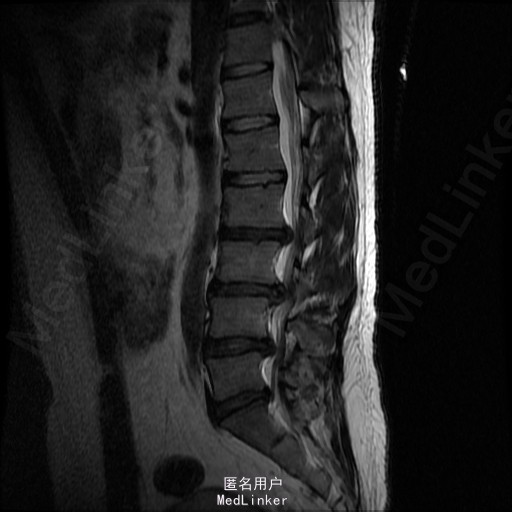

查体:腰部叩痛,腰部活动受限,左侧膝内侧、小腿外侧、内踝、足部感觉减退,右侧小腿、足背感觉减退,屈髋、伸膝、踝背伸肌肌力左侧4级,右侧4-5级,踇背伸、跖屈肌肌力左侧3-4级,右侧4级,双侧膝腱反射+,跟腱反射+,双侧巴氏征阴性,直腿抬高试验左侧40°阳性,右侧阴性。 辅助检查: X-ray:腰椎退行性变,多节段不稳 CT:腰椎间盘突出并椎管狭窄伴钙化,腰2-3,3-4,4-5,腰5骶1 MR:腰椎间盘突出并椎管狭窄,腰2-3,3-4,4-5,腰5骶1 上传受限无法全部上传,见谅

诊断:腰椎间盘突出症并椎管狭窄 处理: 1、完善相关辅助检查,明确诊断,有无手术指证; 2、完善手术评估,有无手术禁忌,手术风险及并发症; 3、在全麻下行腰椎后路多节段减压椎间植骨融合内固定术 4、腰2-3,腰3-4行开窗减压,腰4-5,腰5-骶1行椎间Cage植骨融合